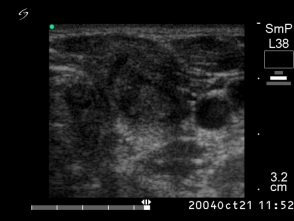

Six months after the therapy (second row of images):

Clinical presentation: the complaints of the patient have disappeared and she did not feel the lesion in the left lobe.

Palpation: the lesion in the left lobe became non-palpable.

Ultrasonography the volume of the treated nodule decreased to less than one-quarter of the original size.

Functional state: euthyroidism with TSH 1.56 mIU/L.